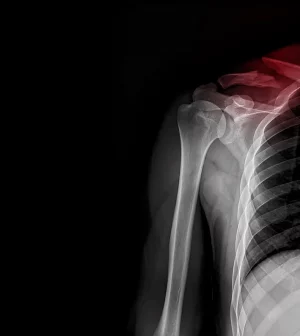

Broken Collarbone Hospitalizations Increase Among Children

More kids are being hospitalized for broken collarbones, a new study has found.

In fact, the hospitalization rate for broken collarbones more than doubled among children between 2014 and 2021, researchers reported.

The hospitalization rate for broken collarbones rose to a high of 2.6% in 2021 from a low of 0.8% in 2014, researchers report.